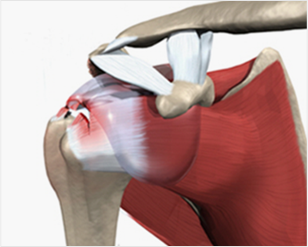

회전근개의 구조

극하근, 극상근, 소원근, 견갑하근 총 4개의 근육으로 구성

회전근개의 파열

근육이 다 끊어지는 경우는 드물며 근육의 일부가 부분적으로

패이거나 늘어지거나 하는 경우가 많다.